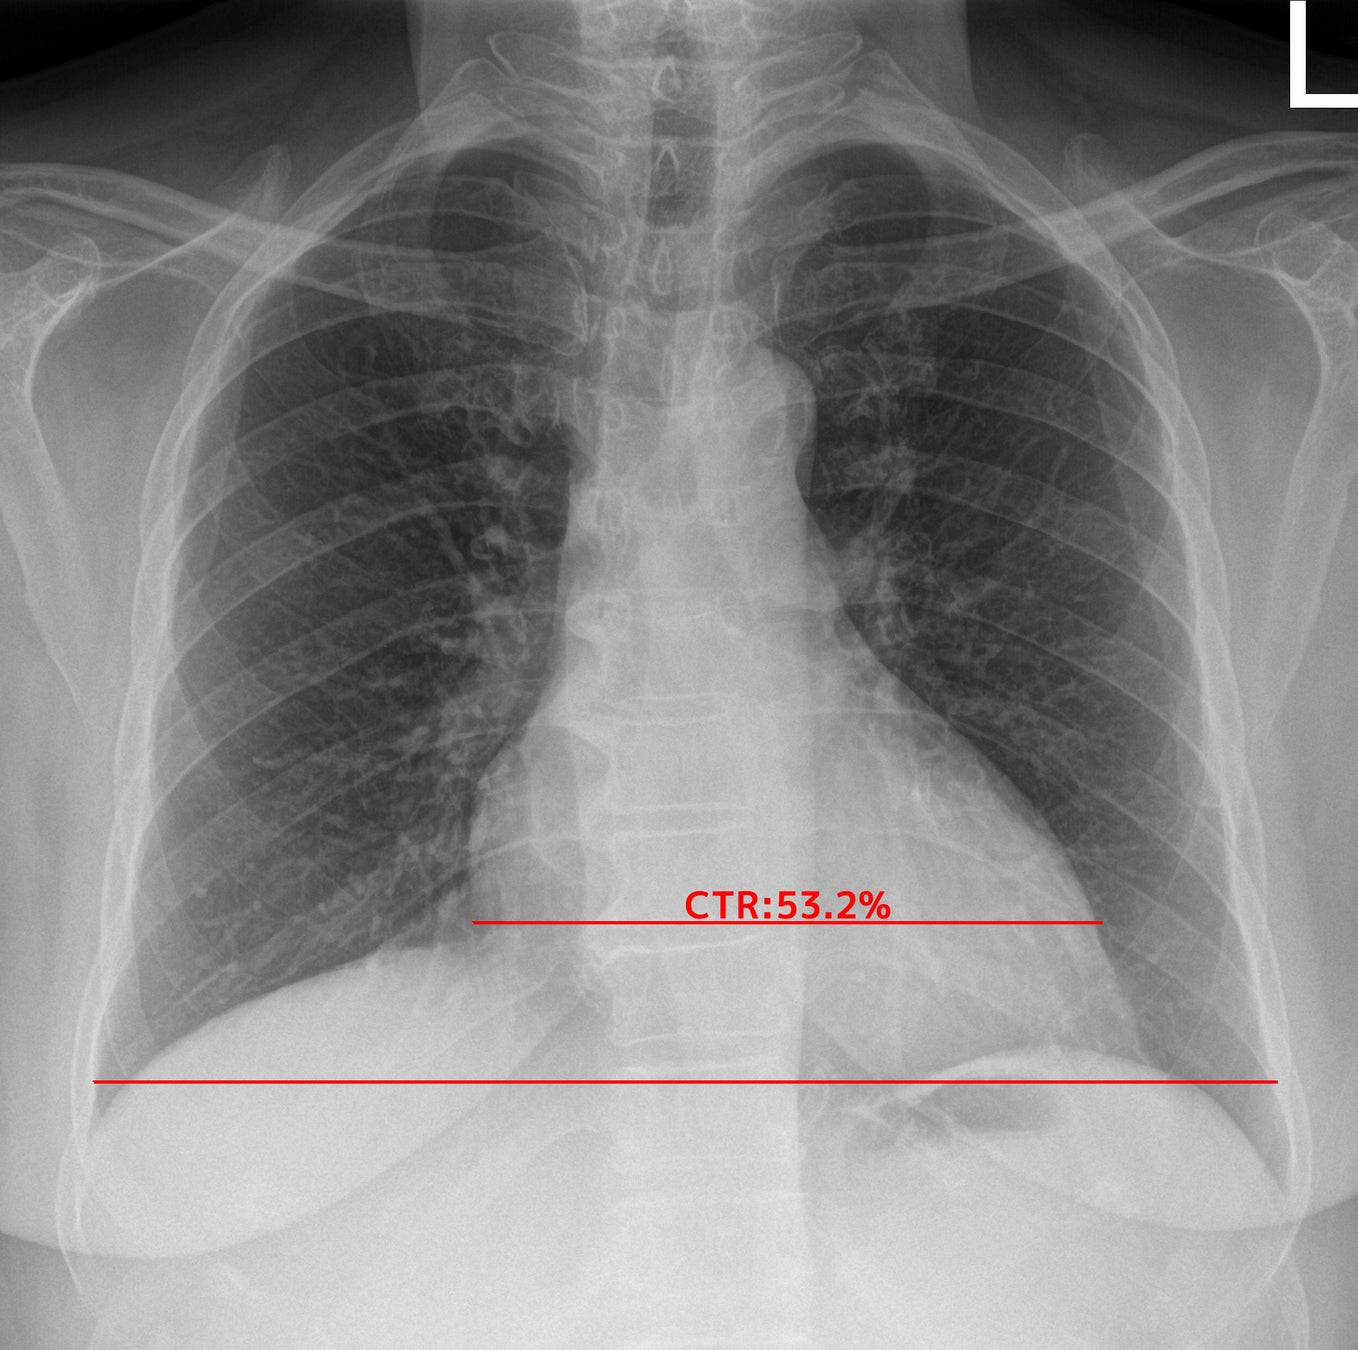

② 心胸郭比(CTR:Cardio-Thoracic Ratio)の計測

肺野の最大幅に対する心臓の最大幅の比[%]を算出し、計測結果が基準値を超えた場合に表示します。

(左はEIRL Chest Screeningによる心胸郭比の計測結果の表示例)

<心胸郭比の拡大について>

心胸郭比は、胸部X線画像での心臓の幅と胸郭の幅の比率です。心陰影の拡大が見られる場合には心不全が疑われ、特に救急現場における心不全の診断に、胸部X線画像は有用であると言われています(5)。